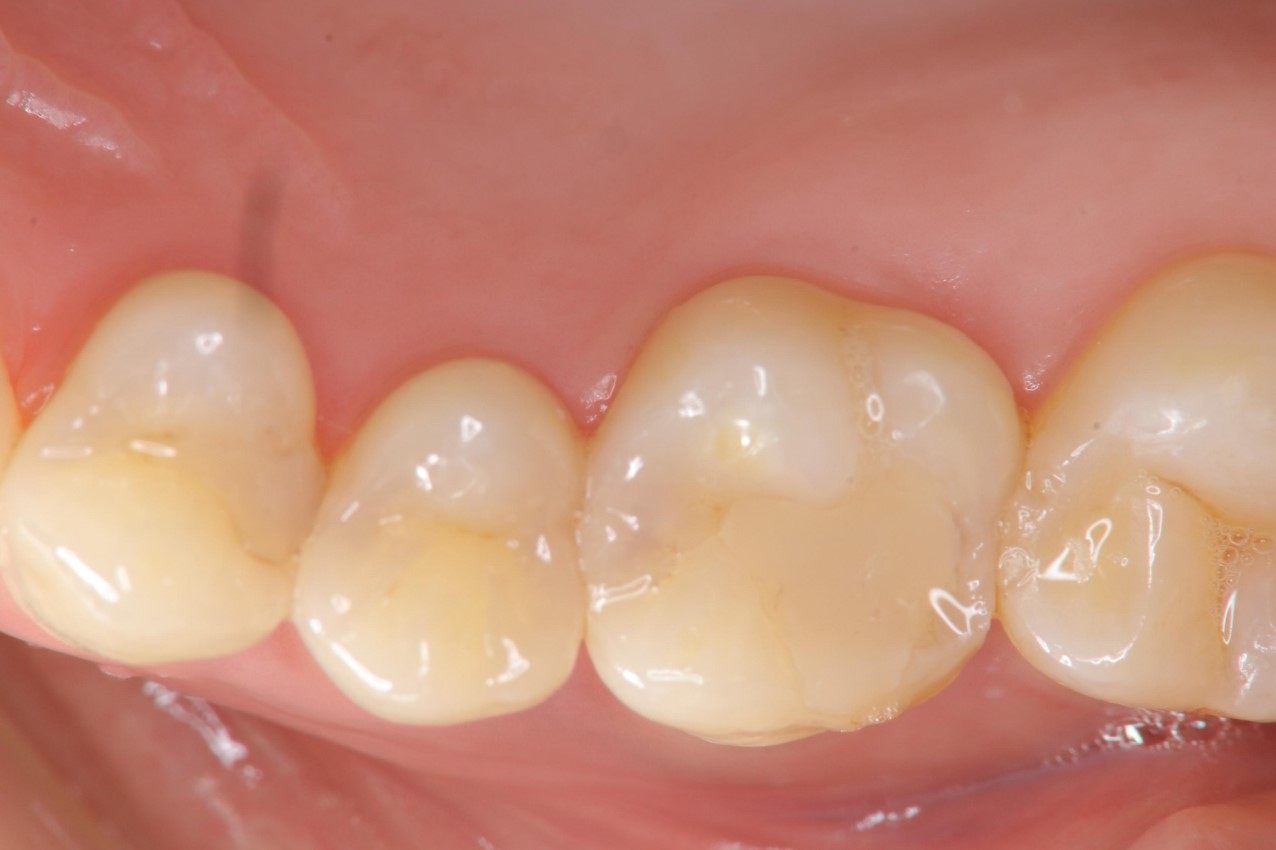

治療前,小臼齒與大臼齒之間冷熱敏感

小臼齒與大臼齒的陶瓷崁體